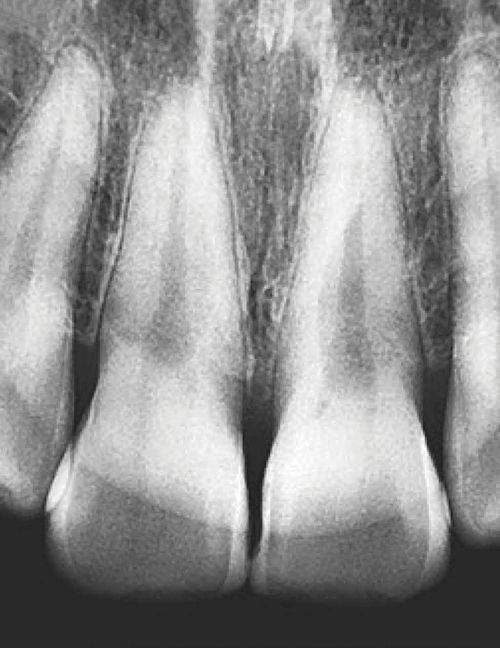

IMAGEM NÍTIDA

Tão nítida quanto o raio-X padrão.

Clareza aprimorada pelo FOCAL SPOT.

70kV, 3mA